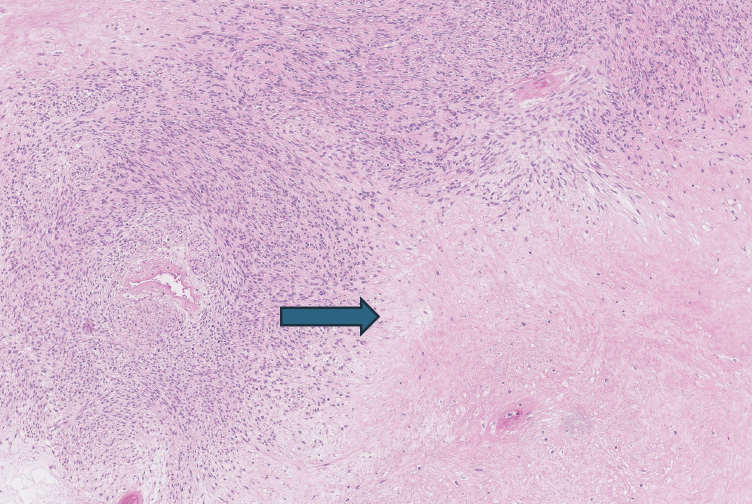

Atlikus histologinį tyrimą, nustatytas gimdos kūno miometre plintantis ląstelingas navikas, suformuotas persipinančių lygiųjų miocitų pluoštų. Navike pastebėta iki 4 mitozių 10 DPRL (didelio padidinimo regėjimo lauke). Buvo matyti atipinės koaguliacinio tipo nekrozės (4 pav.). Limfovaskulinio plitimo neidentifikuota, navikas aiškiai demarkuotas nuo aplinkinio miometro. Navikas imunohistochemiškai nudažytas (1 lentelė). Galutinė patologijos diagnozė ‒ gimdos lygiųjų raumenų neaiškaus piktybinio potencialo navikas (STUMP). Dėl netipinio augimo ir atipinių nekrozių darinys priskirtas neaiškaus piktybinio potencialo lygiųjų miocitų navikų grupei. Aiškių piktybiškumo požymių (branduolių polimorfizmo, didelio mitozinio aktyvumo ar aukšto proliferacinio indekso ar limfovaskulinio plitimo) neidentifikuota. Tikslinga tolesnė pacientės stebėsena kas 6–12 mėn.

4 pav. Koaguliacinio tipo nekrozė (pažymėta rodykle) histologiniame preparate (H&E dažymas, padidinimas ×10)